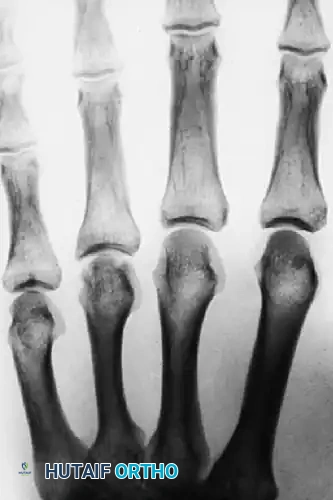

FIGURE 67-39 C: At 4 months postoperatively, radiographs demonstrated early osteonecrosis of the metacarpal head. The sclerosis and early collapse are indicative of the disrupted intraosseous blood supply inherent to this injury pattern.